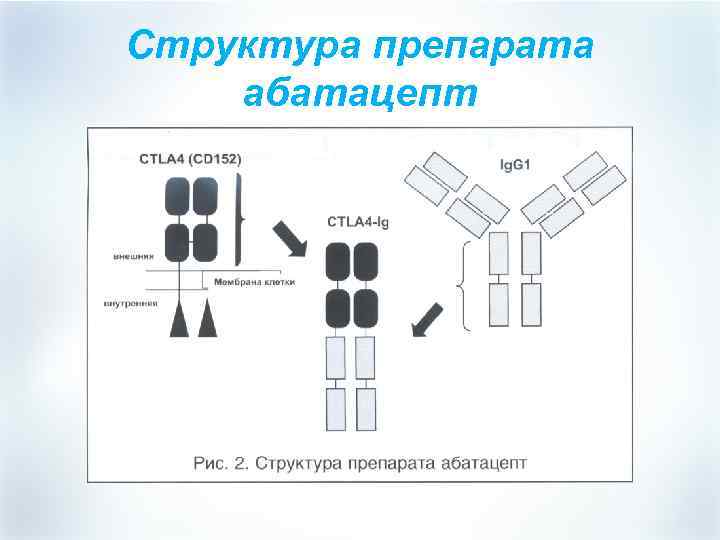

Структура препарата абатацепт

Структура препарата абатацепт